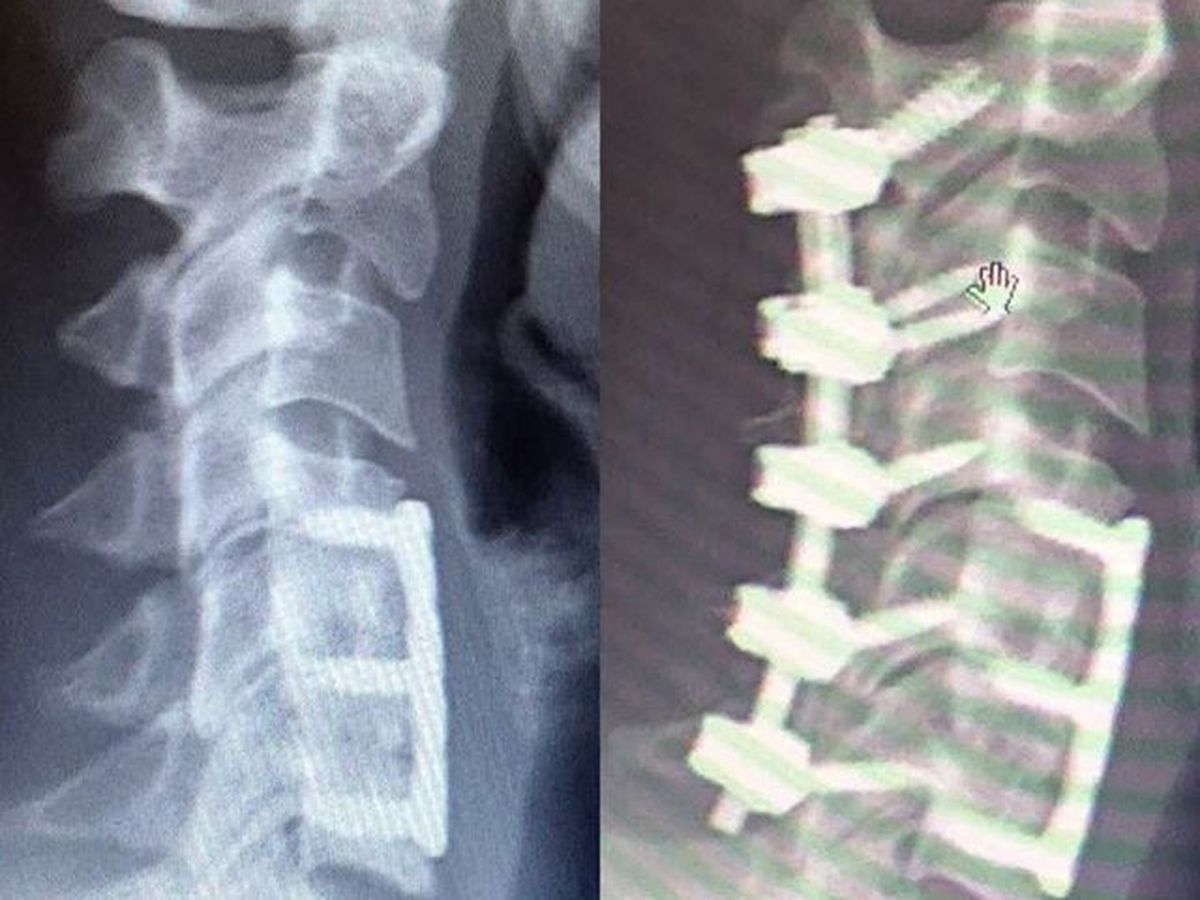

On July 2nd, I'll be having neck surgery. Two additional levels (C2-C4) will be fused, among other things getting fixed in there, and this surgery and recovery will be more intense than my first in 2015. (Details will be added as updates when I'm able.)

Since 2011, I've experienced non-stop severe headaches, neuralgia, and neck/back pain due in part to my neck's structural problems. I also suffer from fibromyalgia and mental illnesses which have contributed to my inability to work reliably over the past few years. The first surgery brought some relief, but as my condition is degenerative and I've explored many traditional and alternative treatments without success, this is my best option, and I feel hopeful and positive that it will bring me some brighter and healthier days in the near future.